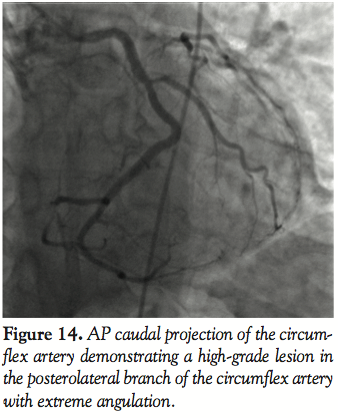

Case 5. A distal lesion in a small posterolateral vessel was successfully treated after very deep engagement of the GuideLiner catheter (Figures 14–16). In the past, this lesion would either be treated medically or with balloon angioplasty, but with the availability of drug-eluting stents in smaller diameters (2.25 mm) and low late loss of 0.1 mm, these patients can be offered relief of their angina as was demonstrated in this case. Caution needs to be exercised with such maneuvers with the catheter.